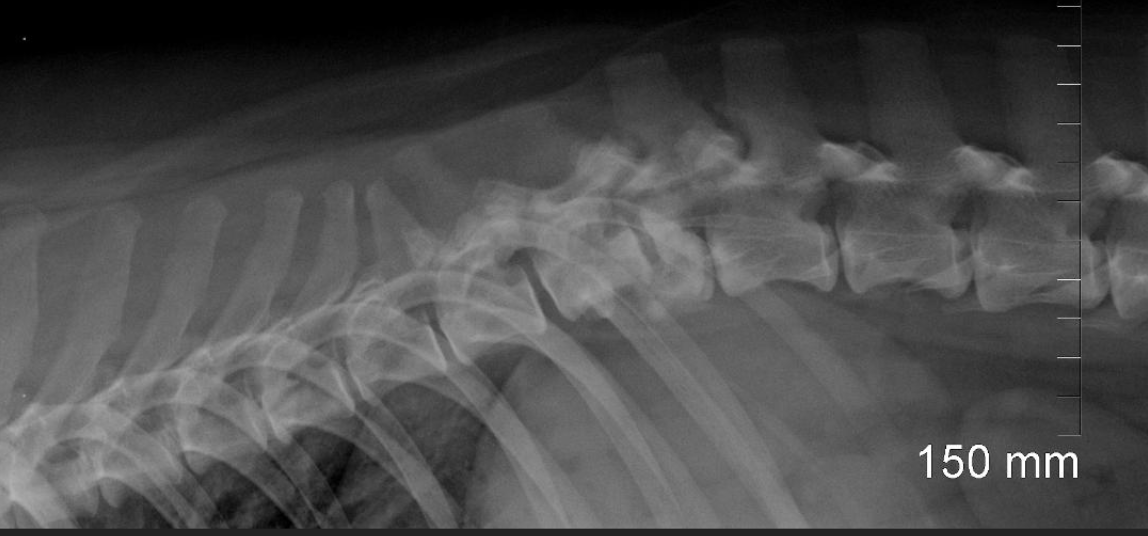

What are the characteristics of radiographs as a diagnostic for spinal trauma?

A

-thoracic rads, survey rads, and spinal rads typically performed

-lateral views okay to perform

-VD view should be taken with horizontal beam; do NOT place patient on back

-fairly good sensitivity at recognizing subluxations and fractures

-okay sensitivity at detecting fragments in spinal canal (compared to CT)

-avoid sedation if possible; can cause relaxation and instability of fractures